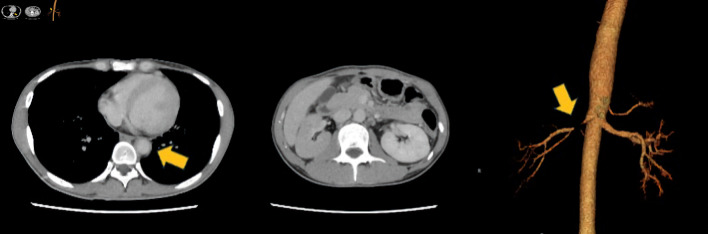

A 23-year-old man was diagnosed with Crohn's disease (CD) of the large intestine after colonoscopy revealed longitudinal ulcers, and pathology revealed non-caseating epithelioid cell granulomas and anal fistulas. The CD relapsed, and therefore prednisolone (PSL) and infliximab (IFX) treatment was initiated. The PSL was gradually tapered. Steroid-free remission was maintained with IFX. The patient subsequently developed a high fever and headache, while CD-related symptoms did not worsen. Laboratory data showed white blood cells at 14,200/µL and C-reactive protein at 17.2 mg/dL. Contrast-enhanced computed tomography revealed thoracoabdominal aortitis, and the patient was consequently diagnosed with Takayasu's arteritis (TA). We therefore again initiated PSL treatment that immediately reduced the fever and headache. The PSL dose was again tapered and the administration of IFX was resumed to maintain CD remission. No further episodes of aortitis relapse were noted after restarting IFX, and the CD currently remains in remission. This is a rare case of TA onset during IFX treatment for CD, and, as such, contributes to the limited literature on such cases. More specifically, this case highlights that when patients with CD present with symptoms such as fever or headache, it is necessary to investigate the possibility of vasculitis.

Abstract Image